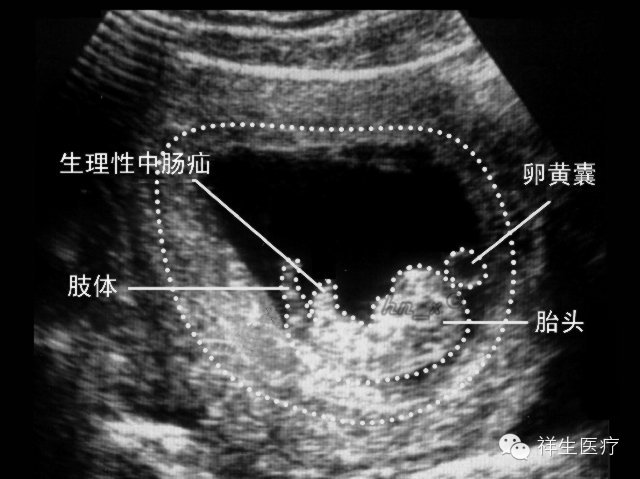

3.孕7周:心脏搏动明显,可显示胎体头极和尾极,并见小肢芽,这时候三维超声会看见宝宝像一个小蚕豆一样。

4.孕8周:初具人形,各部分迅速发展,头颅、躯干、四肢显示越来越清楚。